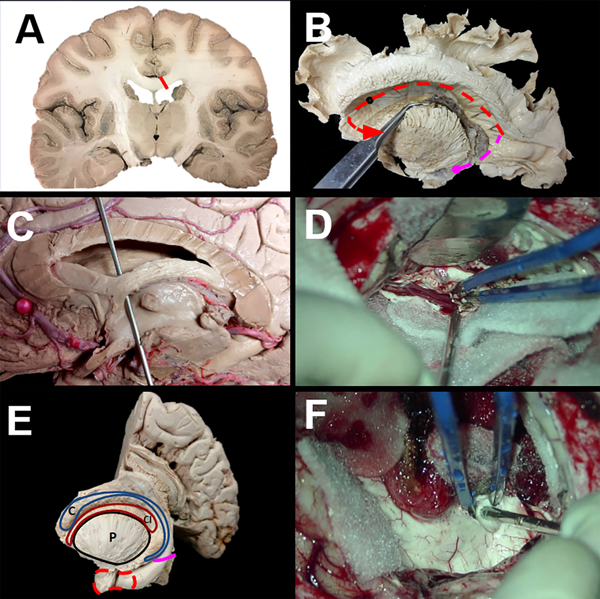

Figura 3. Disecciones representativas e imágenes intraoperatorias que ilustran la técnica de hemisferotomía lateral modificada. (A-D). Desde dentro del ventrículo se incide el cuerpo calloso junto con las conexiones profundas de sustancia blanca entre la rodilla del cuerpo calloso y la corteza frontal orbitaria (A-D). Se desconecta la sustancia blanca adicional entre el cuerpo calloso posterior y el hipocampo posterior (E-F). Se realiza una amigdalohipocampectomía selectiva en la que se extirpa el uncus y la amígdala mediante aspiración subpial. Se retira el hipocampo anterior hasta alcanzar la fisura coroidea, sin dejar aferentes hipocampales.

Para describir de manera más detallada la HPI modificada, se practica una incisión cortical inicial, realizada a lo largo del opérculo frontal paralela al ventrículo y profundizada hasta que se ingresa al asta frontal del ventrículo lateral (Fig. 1 A-B). La apertura ventricular continúa posteriormente hasta el atrio del ventrículo lateral y se continúa posteriormente hasta la extensión anterior del asta temporal (Fig. 1 A-D). En este punto, se identifican, coagulan y ligan las ramas proximales de la arteria cerebral media, distales a los vasos perforantes profundos (Fig. 1 E-F). Usando el plexo coroideo como nuestro límite medial, el opérculo frontal y temporal junto con la ínsula y porciones del núcleo caudado, el tálamo y los ganglios basales se separan y resecan, exponiendo de esta manera el sistema ventricular (Fig. 2 A-D). Desde el asta frontal del ventrículo lateral, se realiza una callosotomía trans-ventricular, desconectando el cuerpo calloso hasta identificar la aracnoides sobre las arterias pericallosas (Fig. 3 A-D). Esta callosotomía transventricular se extiende luego desde el asta frontal hasta la desconexión occipital mesial. Posteriormente, una vez alrededor del esplenio, se extiende la incisión medial anteriormente hasta alcanzar la fisura coroidea, desconectando la fimbria del hipocampo del fórnix (Fig. 3 E-F). Se realiza una desconexión frontal profunda incidiendo justo por delante de los ganglios basales en un plano coronal desde el aspecto anterior del cuerpo calloso hasta la aracnoides de la región orbitofrontal. La identificación del giro recto y el tracto olfatorio proporciona buenos puntos de referencia anatómicos al llegar a la etapa más profunda. Preservar la piamadre basal agrega seguridad a este paso. Finalmente se realiza una amigdalo-hipocampectomía selectiva donde se extirpa el uncus y la amígdala mediante aspiración subpial y se reseca el hipocampo anterior hasta llegar a la fisura coroidea (Fig. 3 E-F).